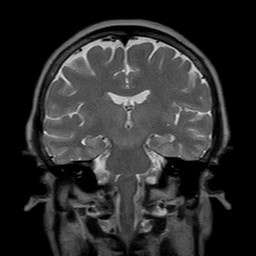

MRI検査は、間隔を空けずに検査しても体は大丈夫ですか?

MRIは磁力を利用する検査です。

放射線ではないので被爆の心配はなく、続けて検査しても身体に影響はないといわれています。